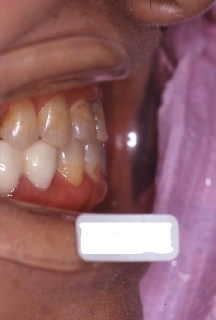

インプラント治療の為の矯正治療症例1

初診時年齢58歳。下顎臼歯部インプラント治療前の咬合改善を目的に来院。

咬み合わせを高くする事で受け口の改善ならびに下顎インプラント挿入スペースを作成した。

矯正治療と並行して専門医によるインプラント治療を行った。

右側面 右側面 右側面